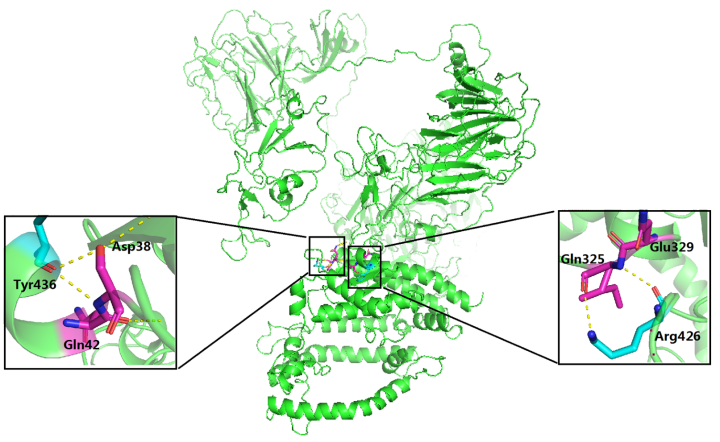

4.3.4 预测药物与蛋白的结合位点

在分子动力学模拟中,预测药物与蛋白的结合位点是一个关键的步骤。这通常涉及到识别蛋白质表面的区域,这些区域可能与小分子药物发生相互作用并形成稳定的复合物。

这种预测通常使用各种计算方法来完成,包括分子对接,比较分析(比如通过比较已知的药物-蛋白质复合物结构),以及使用机器学习和人工智能算法。

分子对接是一种常用的方法,它通过模拟药物和蛋白质之间的相互作用,预测药物可能的结合模式和结合位点。在对接过程中,药物和蛋白质的相对位置和方向会被调整,以寻找能量最低(即最稳定)的药物-蛋白质复合物结构。

这些预测可以帮助研究人员理解药物如何与其目标蛋白质相互作用,以及如何设计更有效的药物分子。然而,需要注意的是,这些预测方法通常需要与实验数据相结合,以验证预测结果的准确性。